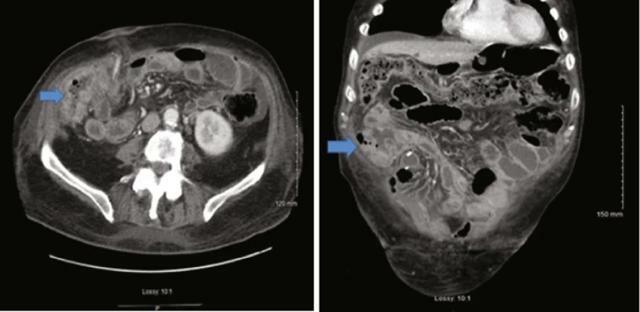

診斷

患者通常表現為 噁心、嘔吐和腹脹。最初通過直立腹部 X 線檢查懷疑該診斷。腹部/骨盆的CT掃描與口服和靜脈造影劑以及識別過渡點或直腸造影劑的缺失可以進行視覺化(圖21.5)。

腹部/盆腔 CT 顯示腸袢擴張,最有可能由腸梗阻引起